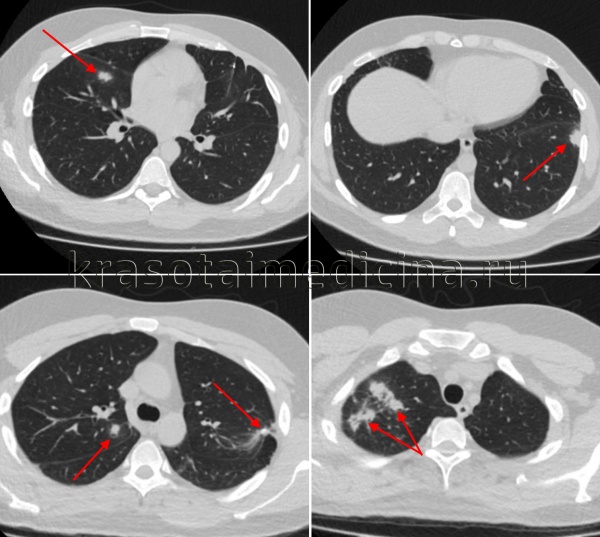

- Рентгеносемиотика диссеминированного туберкулеза легких зависит от клинической формы заболевания. Признаками острого процесса служат наличие в обоих легочных полях множественных однотипных очагов, расположенных симметрично, в виде цепочки по ходу сосудов. При подострой диссеминации очаги имеют тенденцию к слиянию, возможно образование полостей распада. Для хронической диссеминации характерно асимметричное расположение очаговых теней, которые имеют разную форму, величину, очертания, интенсивность в зависимости от срока давности их возникновения. Рентгенография легких, как правило, дополняется линейной или компьютерной томографией.

КТ ОГК. Множественные очаговые поражения верхней и средней доли правого легкого, верхней и нижней доли левого легкого у пациента с диссеминированным туберкулезом.